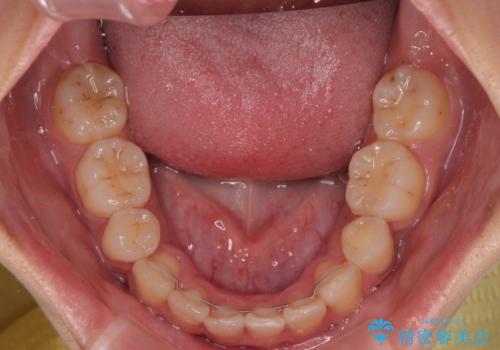

- 前歯の突出感とデコボコを気にして来院された患者様です。

奥歯の噛み合わせをみると、上顎歯列が全体的に前突している状態であり、この咬み合わせのまま歯列を整えると出っ歯になってしまう可能性がありました。

上下の前歯が接触する仕上がりとなったので、横顔の印象が大幅に改善されました。